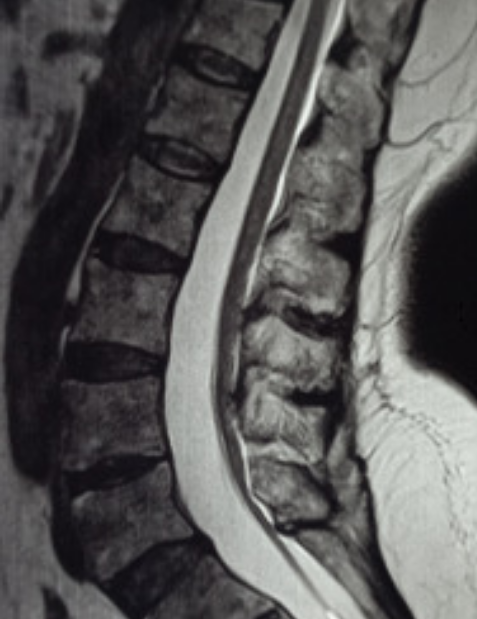

MRI Scan

Syringomyelia